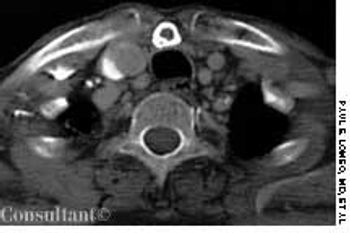

A 31-year-old man with a history of traumatic brain injury was hospitalized because of failure to thrive, constipation, and intermittent diarrhea with soiling.